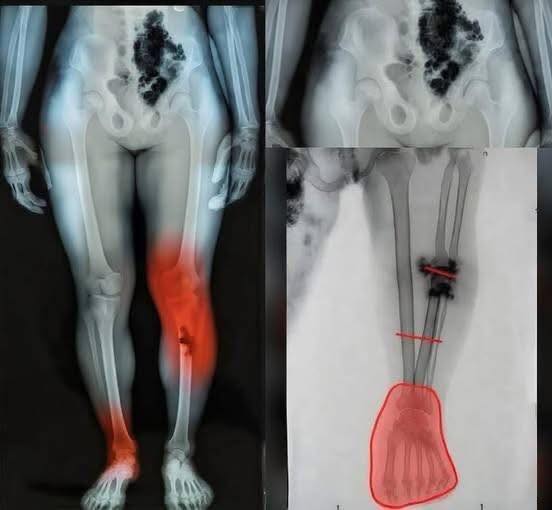

At first, people thought it was just another phase of recovery—aches, fatigue, maybe a bit of lingering discomfort. But then something different started happening. Individuals began reporting unusual pain in specific areas, particularly in the legs and lower body, symptoms that didn’t quite match what they had been told to expect. The pattern was subtle at first, but it quickly caught attention.

Medical professionals began looking deeper, trying to understand whether these cases were isolated or part of a broader trend. Some patients described a burning sensation, others a deep ache that seemed to come and go without warning. While not everyone experienced it, the consistency in certain reports was enough to raise concern and prompt further investigation.

Experts emphasize that the human body can respond in complex ways after illness, especially when the immune system has been heavily activated. In some cases, inflammation can linger or affect areas that weren’t initially involved. That doesn’t necessarily mean something dangerous is happening, but it does highlight how much researchers are still learning about long-term effects.

At the same time, doctors are urging people not to panic or jump to conclusions based on isolated images or claims online. Not every symptom is directly linked, and not every experience follows the same path. The key message remains clear: if something feels unusual or persistent, it’s important to get it checked rather than relying on speculation.